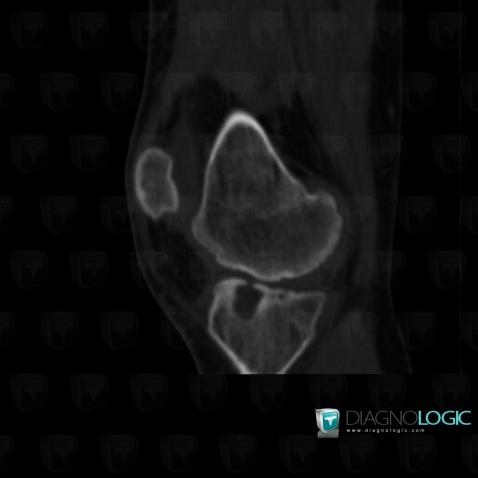

Hemophilia, Femorotibial joints - Intercondylar notch, CT

Here is the specific information in the key image above:

- Diagnosis Hemophilia, Location(s) Femorotibial joints - Intercondylar notch, with gamuts